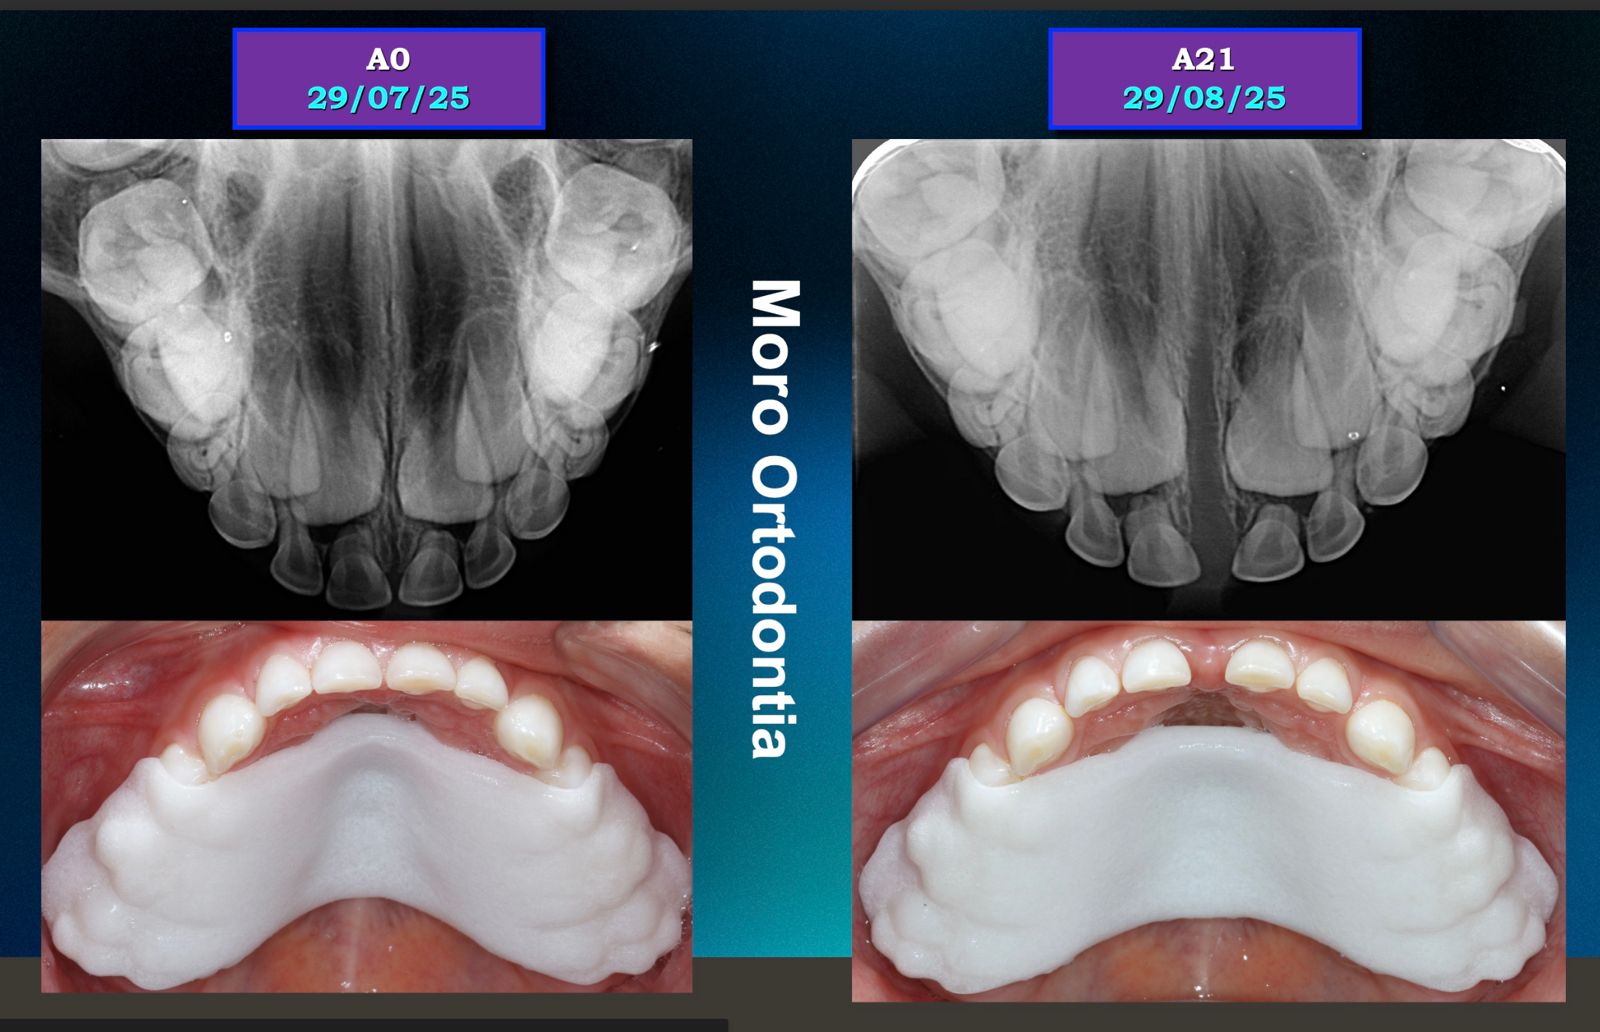

Novo Palatal Expander – Expansor Palatino Digital

O Novo Palatal Expander é uma evolução dos aparelhos expansores tradicionais. Integrado à tecnologia Invisalign e ao escaneamento digital iTero, ele permite ampliar o arco dentário de forma precisa, controlada e mais confortável para a criança.

6. Quanto tempo dura o tratamento?

Geralmente de 4 a 6 meses, dependendo da necessidade de expansão.